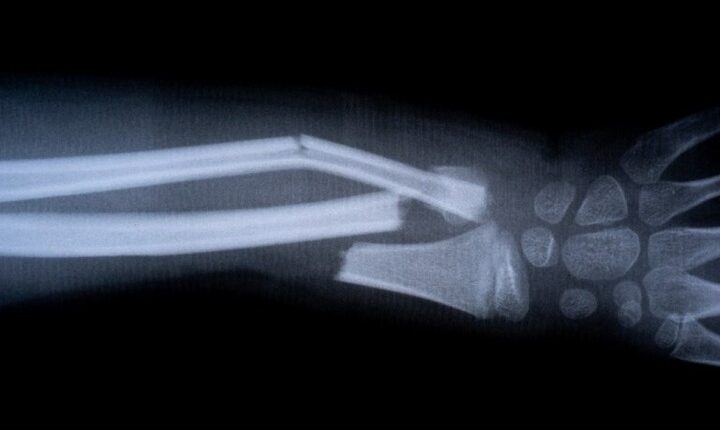

JUST IN: Chinese scientists develop ‘bone glue’ that heals fractures in minutes

Scientists in China have unveiled a groundbreaking “bone glue” that can heal fractures within minutes, cutting down recovery times that would normally take months. The product, called Bone-02, was developed by a research team aiming to reduce the need for invasive orthopedic surgeries that often involve metal plates and screws, according to New York Post.